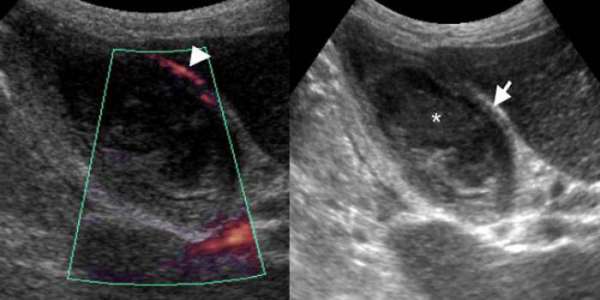

Диагностика лопания желчного пузыря включает в себя обследование пациента, анализы крови и мочи, ультразвуковое исследование, компьютерную томографию и другие методы.

- Проведение ультразвукового исследования брюшной полости призвано определить локализацию поражения (разрыва) стенки органа и наличие жидкости в самой брюшной полости.

- Такой инструментальный метод исследования, как лапароскопия, предназначен для окончательного подтверждения диагноза разрывов желчного пузыря. Процедура часто назначается в случае, если непосредственно стенки желчного пузыря не повреждены, а симптоматика вызвана наличием пузырно-кишечных свищей.

Обострение состояния вызывает заброс микробов в желчный пузырь из кишечника и развитие инфекции. Часто такой разрыв выявляется только при обследовании посредством УЗИ или лапароскопии.